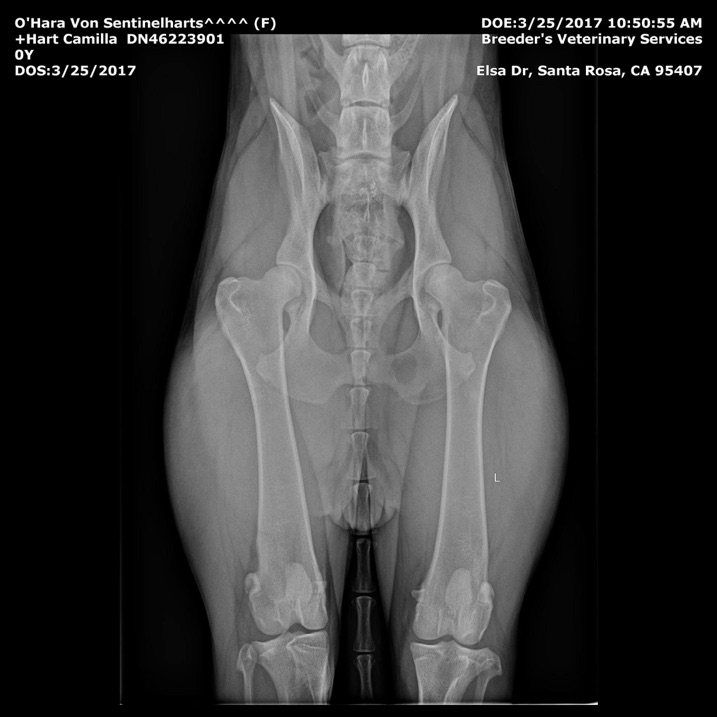

Hips- OFA GOOD GS-99766G24F-VPI

Elbows- OFA Normal  GS-EL38352F24-VPI